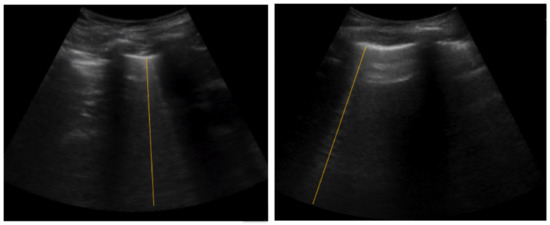

:1. Introduction